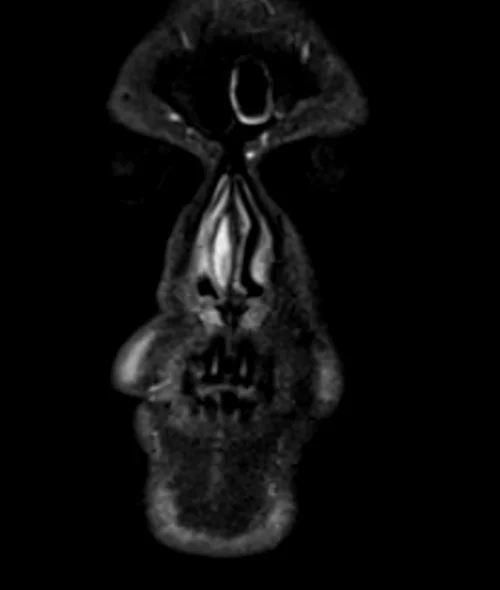

MRI face STIR coronal images